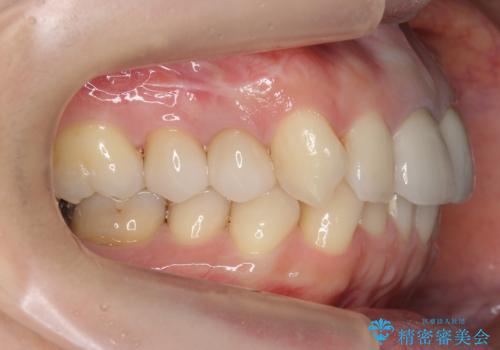

奥歯がないまま過ごしていたら前歯もぐらぐらしてきた 60代女性

[前歯のグラつき] 根本的な前歯の審美治療を希望